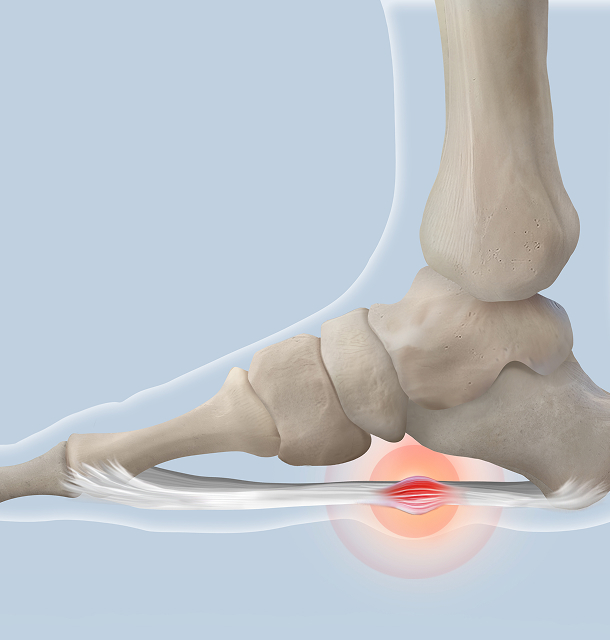

족저근막염

발바닥의 통증을 유발하는 염증성 질환

Plantar Fasciitis

족저근막염이란?

족저근막이 반복적인 미세 손상을 입어 근막을 구성하는 콜라겐의 변성 및 염증이 발생한 상태

족저근막염 원인

- 1급격한 체중 증가

- 2오래 서 있는 직업

- 3평발, 요족

- 4하이힐, 플랫슈즈 착용 등

족저근막염 증상

발뒤꿈치 안쪽에 찌르는

듯한 통증이 있음 -

발 뒤꿈치 안쪽 누를 때,

발바닥을 쫙 펼 때 통증이 있음 -

앉거나 누워 있다가 첫발을

디딜 때 통증이 심함 -

발 뒤꿈치를 만지면 통증 /

짧은 보행에도 통증